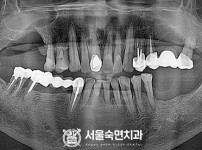

임플란트-전후사진2